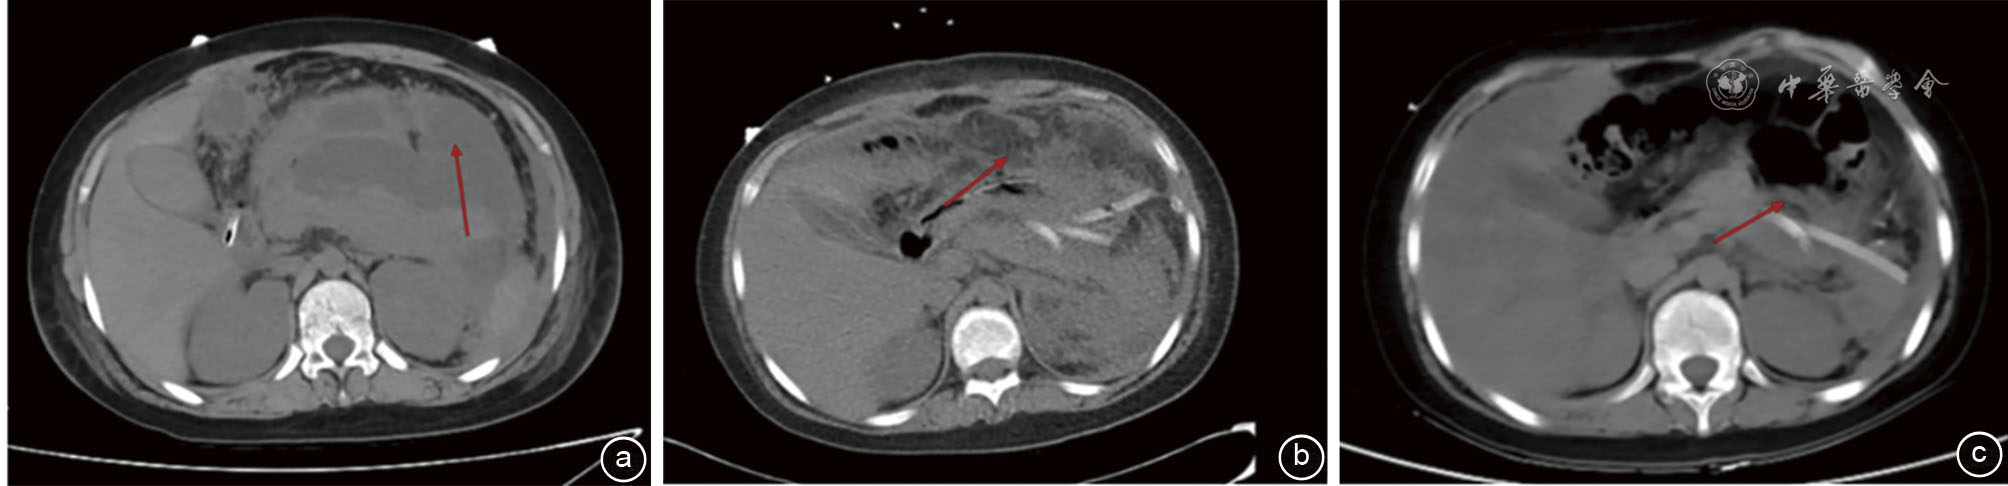

图1 一例儿童重症急性胰腺炎腹部手术前后CT检查图像 注:a为术前CT平扫示胰腺饱满,轮廓不清,腹腔大量积液;b为术后1周胰周包裹性积液基本消失,腹腔盆腔积液减少;c为术后3个月胰周渗出基本消失,腹膜炎减轻(箭头所示)